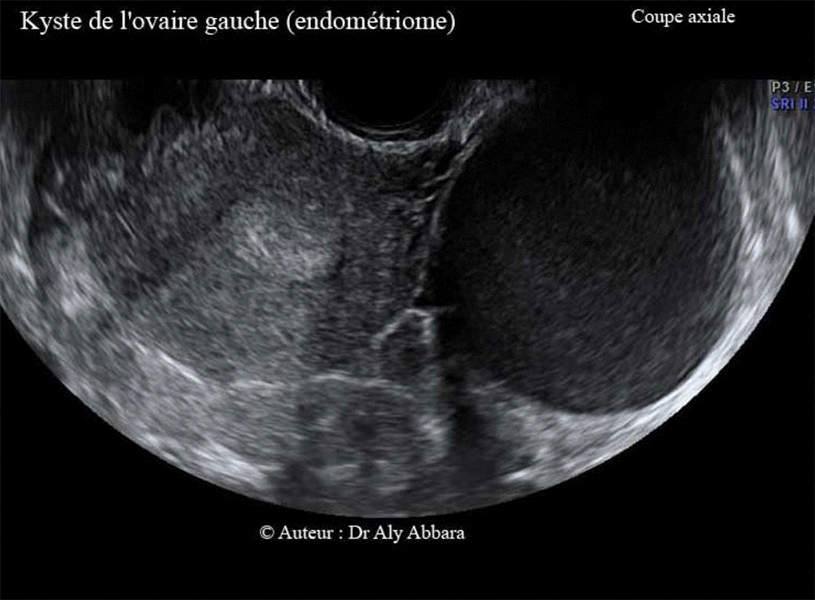

Volumineux kyste endométriosique (endométriome) de l'ovaire gauche - Echographie

Endométriome ovarien gauche

• Images échographiques montrant l'aspect ultra-sonore d'un endométriome (kyste endométriosique) ovarien gauche de 104 cm3 de volume.

Il s'agit d'une formation kystique uniloculaire mesurant (71,7 x 52,5 x 52,6 mm) ; à paroi régulière, de 2 à 3 mm d'épaisseur, avec une seule végétation endophytique (évoluant vers l'intérieur de la cavité kystique) apparaissant sur son endothélium postérieur sous forme de polype de 6 mm de grand axe, pédiculé et ne montrant pas d'activité vasculaire au Doppler.

Le contenu du kyste est liquidien, hypo-échogène faisant penser, soit à un contenu visqueux, mucoïde (kyste mucineux) ; soit au liquide formé du sang lysé, concentré et épaissi, prenant un aspect chocolat

oïde (comme le chocolat fondu), qu'on voit normalement dans les kystes endométriosiques (endométriomes).

Biologiquement les dosages des marqueurs tumoraux sériques chez la patiente sont normaux en dehors d'un taux élevé de CA 125 (76 UI/l ; norme : < 35 UI/L).

Il s'agit d'une femme âgée de 32 ans, mère d'un enfant de 4 ans, ne souffrant d'aucune douleur spontanée ou provoquée, pendant ou en dehors des règles ; elle consulte pour une infertilité secondaire de deux ans ; c'est l'examen clinique qui permet de découvrir la présence de ce kyste.

L'exploration opératoire, et l'examen anatomopathologique confirment la nature histologique de ce kyste ; il s'agit d'un

endométriome isolé (kyste d'endométriose), sans aucune d'autre lésion abdomino-pelvienne ou péritonéale individualisable associée et sans phénomènes adhérentiels intra-abdominal.